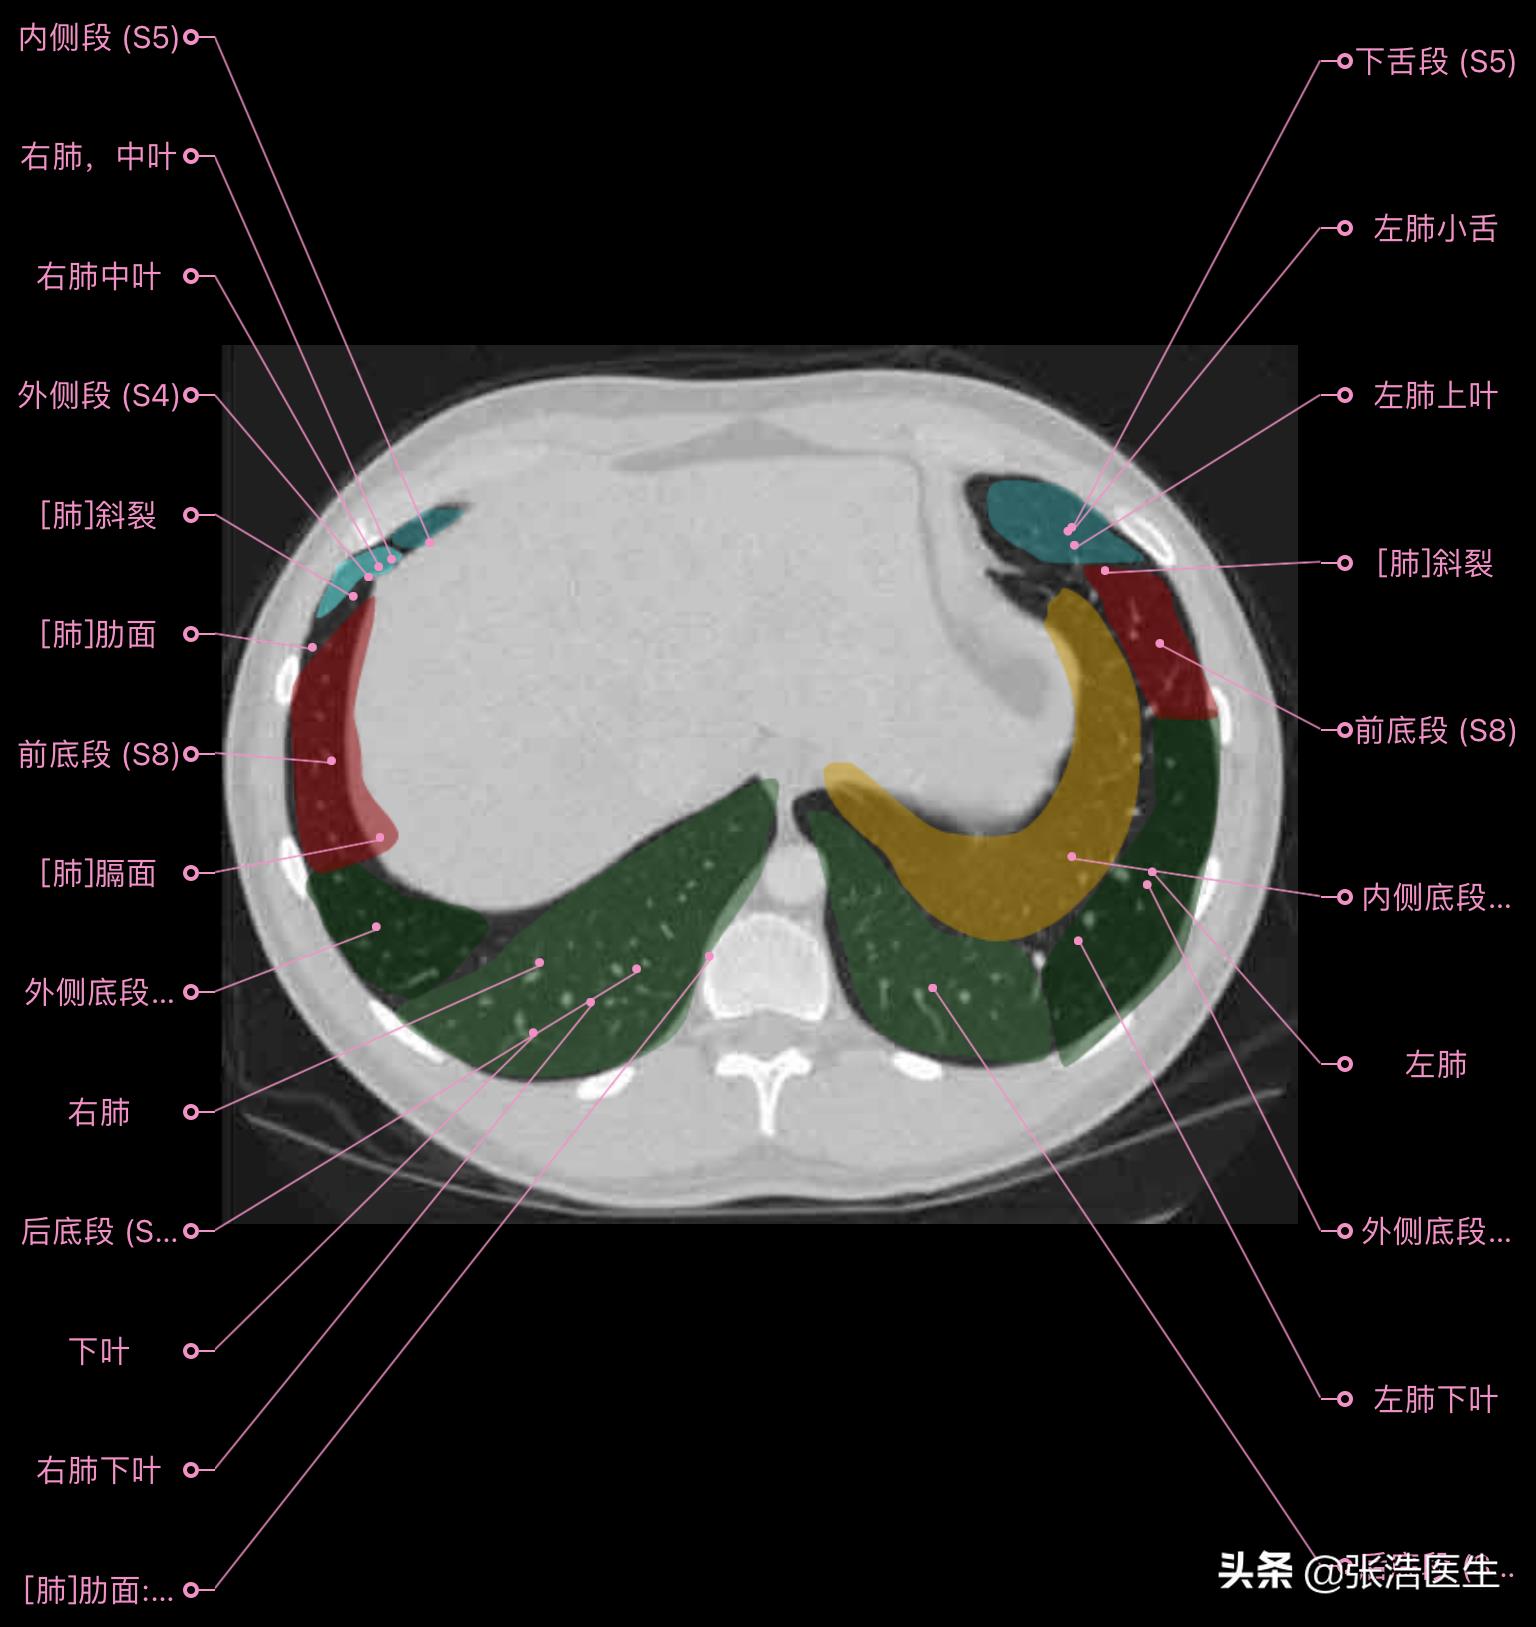

肺部CT横断面高清解剖图谱(图层6)